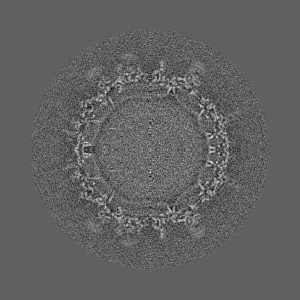

Cryo-EM structure of Dengue virus serotype 2 in complex with antigen-binding fragments of human antibody 2D22

Single-particle6.5 Å

Sample: Dengue virus serotype 2 strain PVP94/07 (a clinical isolate) complexed with Fab fragments of human antibody 2D22.

DENGUE VIRUS. Cryo-EM structure of an antibody that neutralizes dengue virus type 2 by locking E protein dimers.